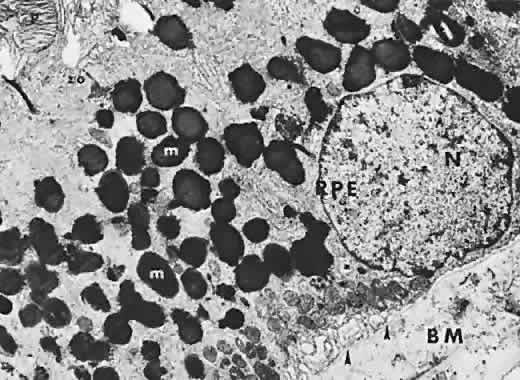

The RPE also functions as an optical barrier because of the presence of pigmented melanosomes (Fig. 6). The density of this pigment varies with retinal location; it is greatest in the foveomacular region and least anterior to the equator. There are more pigmented epithelial cells per unit area in the foveomacular region than in the periphery. Posteriorly, the cells are tall and columnar, with several layers of melanosomes crowded together. Anteriorly, the cells gradually become flatter and more cuboidal, with a corresponding loss of relative pigment concentration (Fig. 7). In any normal eye, regardless of the comparative fundus color, the greater pigmentation in the foveomacular area gives this zone a darker clinical appearance when compared with the remainder of the posterior pole and periphery.

Fig. 6. Fine structure of retinal pigment epithelium (RPE), showing heavy concentration of pigment granules, melanosomes (m), nucleus (N), intricate basal infoldings (arrows), and zonula occludens (zo). Tip of a photoreceptor cell (P) can be seen at apical side of RPE; Bruch's membrane (BM) can be seen on basal side of RPE (transmission electron microscopy, × 11,200).